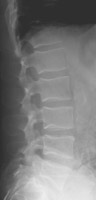

Compression fractures of the spine are common in elderly and osteoporotic patients. They result from anterior or lateral flexion. The typical appearance is loss of height of the anterior aspect of the vertebral body with preservation of the posterior elements and generally the posterior aspect of the vertebral body. On the frontal view, there may be subtle deviation of the paraspinous line due to edema. Differentiation from a pathologic fracture of the spine due to a metastasis is usually of clinical concern, but simple compression fractures are usually due to osteoporosis.

- Click on the image for a larger versionCLateral radiograph of the lumbar spine. This is an image from a different patient and shows a severe compression fracture of the T12 vertebral body.